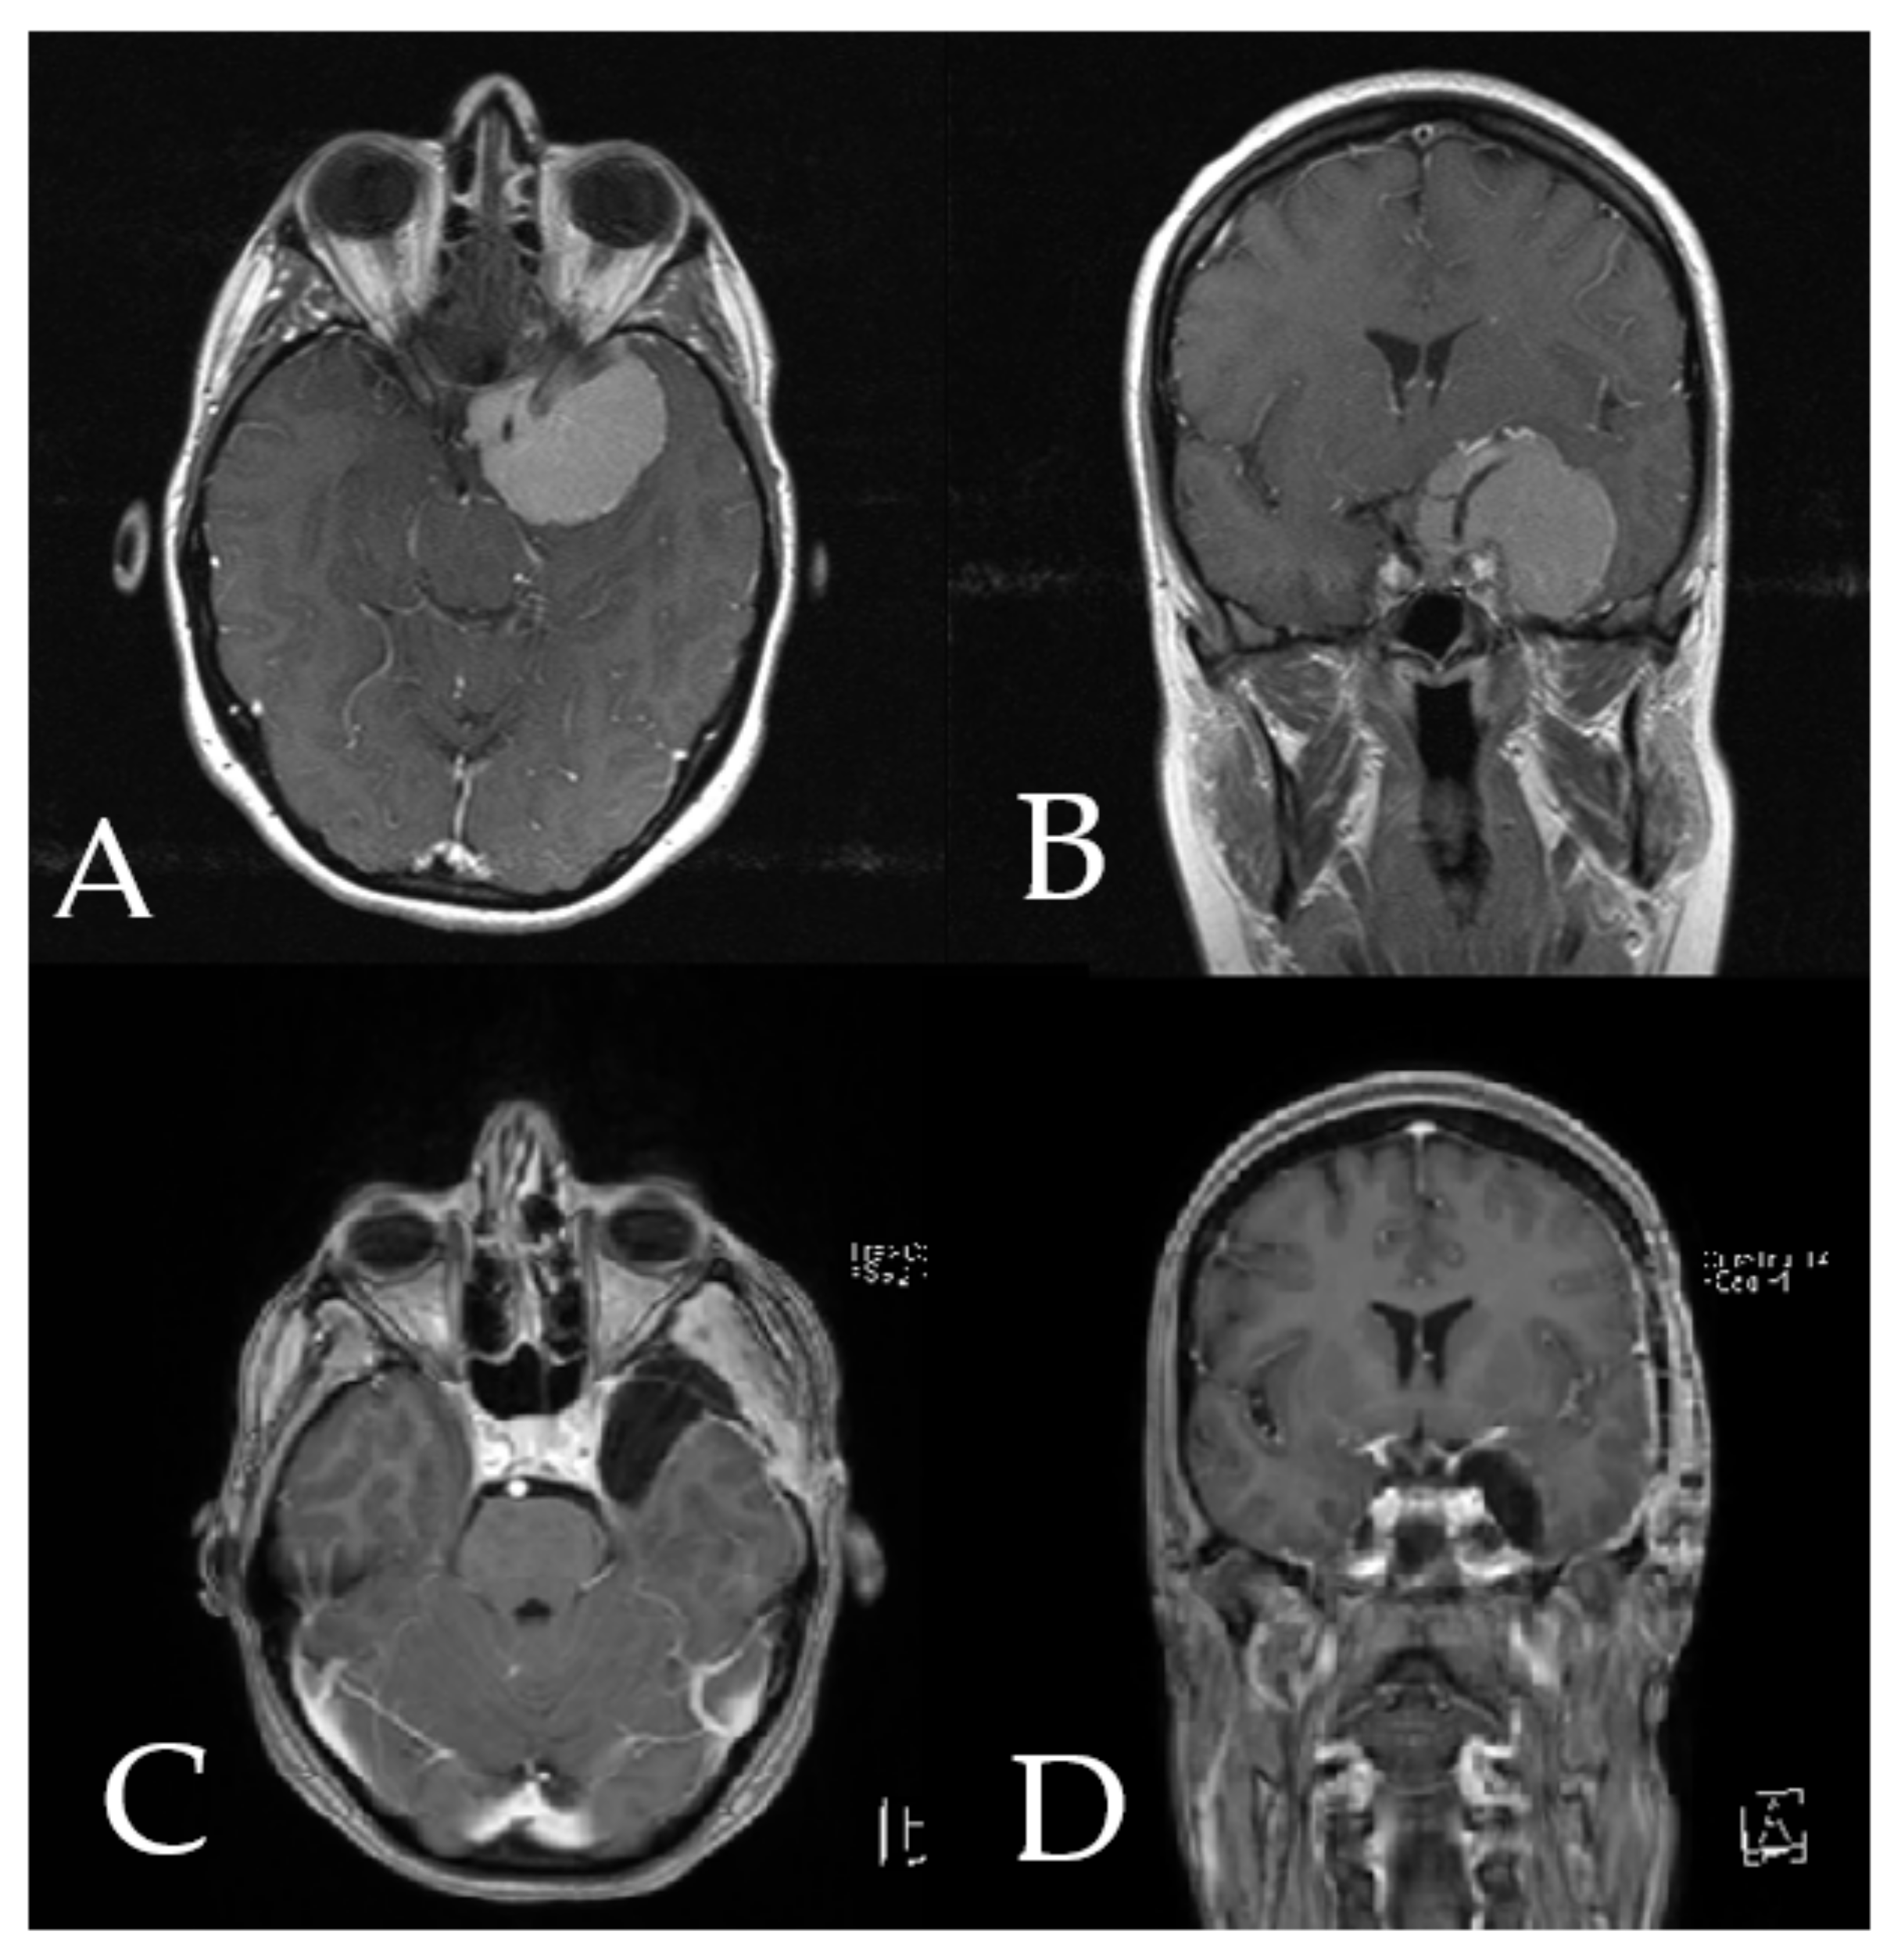

Figure 6. Preoperative axial (A) and coronal (B) T1-weighted post-contrast MRI of the head in patient number 9 shows a large medial sphenoid wing meningioma with encasement of carotid and cerebral medial artery. Postoperative axial (C) and coronal (D) postcontrast MRI of the head shows complete resection of the tumor.

Case 2: A 38-year-old female patient with giant medial sphenoid wing meningioma on the left side presented with vertigo (patient number 9). GTR was performed using iCT-based navigation registration and microscope-based AR. Figure 5 demonstrates the intraoperative view throughout the resection and Figure 6 shows preoperative and postoperative MRI imaging. The patient recovered fully and had no neurological deficits. Operative video has been added to the Supplemental Materials: Patient number 9.